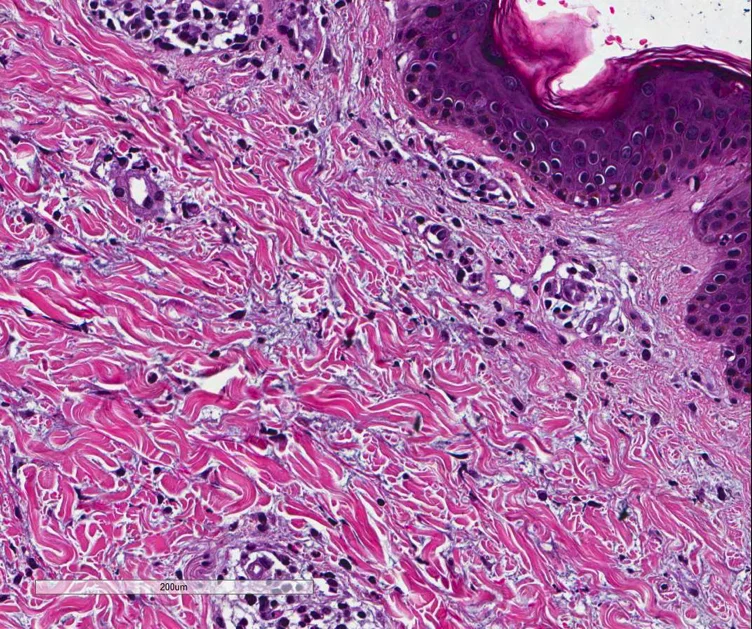

April pathology Case

Clinical history: 20 year old female. Quotidian spiking fevers, arthralgia and elevated serum ferritin.